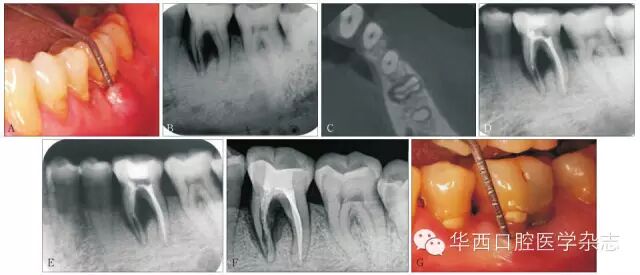

病例2:男性,66岁。主诉:左下后牙冷热刺激痛2月。检查:36牙未见明显龋损或隐裂,有延迟痛,冷(++),叩(+),松Ⅰ°;近中颊侧牙龈肿胀,探及5 mm牙周袋,袋内溢脓(图8A)。根尖片见近中根管径增宽,根周及根分叉牙槽骨吸收, CBCT轴位见颊舌向折线(图8BC)。诊断:36近中根折裂。治疗:经患者知情同意,选择生物治疗。局麻下调、开髓,近中根管手动轻度预备至牙根纵折平面,远中根管常规预备,1.5%NaClO 20 mL(每根管),轻柔冲洗5 min0.9%生理盐水20 mL(每根管),轻柔冲洗5 min,诊间封CaOH)2糊1周后复诊,局部症状减轻,17%乙二胺四乙酸(ethylenediamine tetraacetic acidEDTA)溶液反复轻柔冲洗根管行根管充填。具体步骤如下:1)远中根常规热牙胶充填;2)刺激根尖出血充盈牙根折裂累及区;3)近中根生物活性材料注射充填(图8D);4)髓室放置湿棉球,暂封;51周后复诊,垫底+树脂充填修复(图8E)。6月后随访:主观症状明显地减轻,牙龈肿胀溢脓消失,叩(±),松(-),未探及明显牙周袋(图8FG)。

A:初诊口内见牙龈肿胀溢脓,牙周深袋;BC:根尖片及CBCT轴位见36近中根折裂;D:生物活性材料注射充填后暂封;E:垫底+树脂充填修复后;F6月后复诊根尖片见根周骨质密度增高,提示有骨质修复;G:复诊时口内示牙龈肿胀溢脓消失。

8 病例2